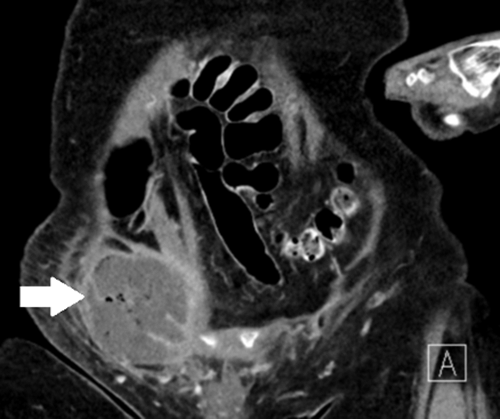

We describe the case of an 84-year-old female presenting with a right Amyand’s hernia containing a perforated appendix and a large associated abdominal wall abscess. Her medical history includes hypertension, dementia, and no prior surgical interventions. She presented to the emergency department with a one-week course of progressive right lower quadrant pain, nausea, and chills. During the initial evaluation, she was found to be febrile. Her physical exam noted right lower quadrant tenderness with overlying skin erythema and fluctuance to palpation. A computed tomography (CT) of the abdomen and pelvis showed an incarcerated, perforated appendix coursing into the right inguinal canal with an adjacent 6.9 × 4.5 × 7 cm abdominal wall abscess. She was admitted to the hospital for intravenous antibiotic treatment and percutaneous drainage of the abscess by interventional radiology. The abscess culture grew Escherichia coli and Streptococcus anginosus. On hospital day 10, she was discharged to a nursing facility for drain care, where an oral course of amoxicillin-clavulanate for 14 days was completed. Approximately one month later, the patient returned to the operating room for an interval laparoscopic appendectomy. Upon exploration of the abdomen, the appendix was found to be incarcerated within the right inguinal hernia. Once successfully reduced, a standard laparoscopic appendectomy was completed. No fluid collections were evidenced in the abdomen or abdominal wall. A large right inguinal defect was visualized, and the decision to pursue a definitive hernia repair at a later stage was made, given her high risk for mesh infection. Her postoperative course was uneventful. During her postoperative follow-up, her son and heath care proxy decided not to pursue hernioplasty, given her recent functional decline and high morbidity risk.

Figure 1. CT Scan of Inflamed Appendix With Tip Inside Right Inguinal Hernia. Published With Permission